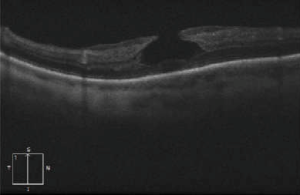

OCT imaging showing the partial loss of inner foveal tissue is diagnostic. Fundus autofluorescence can also show hyperautofluorescence due to a window defect in the macular area from the loss of foveal tissue.

OCT diagnostic criteria for LMH have undergone multiple changes over time. The most widely used 2006 criteria adopted by the International Vitreomacular Traction Study Group included:

- An irregular foveal contour;

- A break in the inner fovea;

- Dehiscence of the inner foveal retina from the outer retina;

- The absence of a full-thickness foveal defect with intact foveal photoreceptors[15][16].

Govetto et al. subsequently divided LMH into “tractional” and “degenerative” categories with a minimum of 3/5 diagnostic criteria for each type (see table)[4]. If it fails to correspond to either category, the lesion is classified as “mixed”.

The newest consensus made by Hubschmann et al. distinguishes LMH presenting with tractional, contractile ERM by identifying them as ERM foveoschisis (ERMF)[16]. LMH presenting with degenerative configuration are simply referred to as LMH.

| OCT imaging |

OCT is the gold standard for diagnosing and managing LMH with findings as described above. Fundus autofluorescence can also be performed which shows hyperautofluorescence through loss of foveal tissue leading to a window defect.